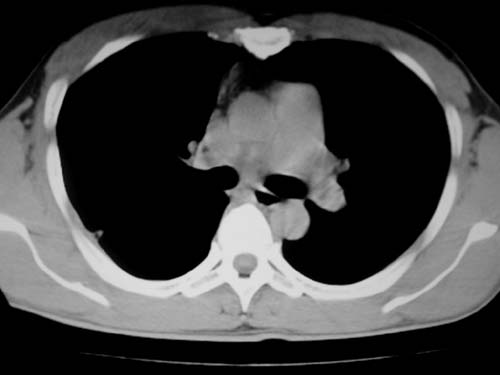

标题: CT19540: 31岁。自述结核性胸水治疗两个月后,在外院拍x线发 [打印本页]

标题: CT19540: 31岁。自述结核性胸水治疗两个月后,在外院拍x线发

右侧胸壁结节状软组织影伴相应肺叶内受侵,伴右侧胸腔积液。考虑:结核性可能大。

支持 右侧胸壁结节状软组织影伴相应肺叶内受侵,伴右侧胸腔积液。考虑:结核性可能大。

右侧胸壁结节状软组织影伴相应肺叶内受侵,伴右侧胸腔积液,结合临床,首先考虑结核。

考虑结核性胸膜炎,胸膜肥厚,不除外胸膜间皮瘤可能,建议复查。

1)考虑右侧结核性胸膜结节。2)右侧胸膜增厚+包裹性胸腔积液。